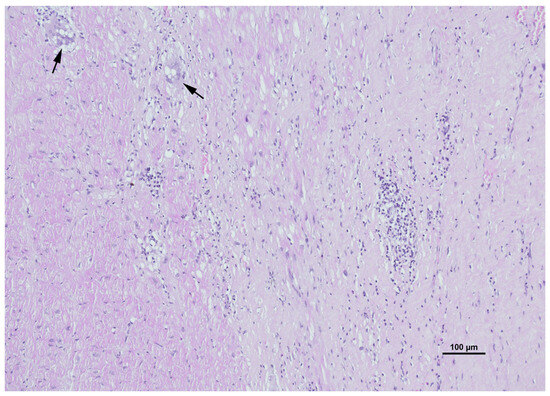

Cardiac sarcoidosis (CS) is a critical and frequently underdiagnosed phenotype of sarcoidosis, characterized by non-caseating granulomatous infiltration of the myocardium. This review synthesizes current knowledge regarding the pathogenesis, diagnosis, and management of CS. The disease manifests with a heterogeneous clinical spectrum ranging from asymptomatic conduction abnormalities to life-threatening ventricular arrhythmias and heart failure. Diagnosis remains challenging due to the patchy distribution of granulomas, which limits the sensitivity of endomyocardial biopsy. Consequently, a multimodal diagnostic approach is essential, integrating advanced imaging modalities such as cardiac magnetic resonance (CMR) with late gadolinium enhancement (LGE) and 18F-fluorodeoxyglucose positron emission tomography (FDG-PET). These tools not only facilitate detection but also enable the differentiation of active inflammation from chronic fibrosis. Histopathological assessment, supported by specific immunophenotyping and electron microscopy, remains the gold standard for confirming diagnosis and excluding mimics like giant cell myocarditis or infectious granulomatous diseases. Management requires a multidisciplinary strategy combining immunosuppressive therapy, primarily corticosteroids and steroid-sparing agents, with guideline-directed cardiac care, including implantable cardioverter-defibrillators for arrhythmia risk stratification. Emerging biomarkers and artificial intelligence-driven imaging analysis promise to further refine risk stratification and therapeutic monitoring, advancing precision medicine in this complex disorder. Full article

Show Figures

Figure 1